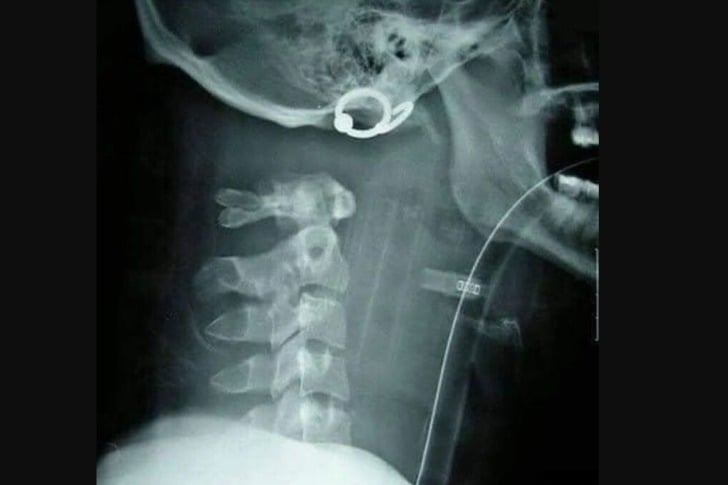

#37 Decapitación interna

Lo más probable es que esta persona haya recibido un impacto en la mandíbula inferior, lo que resultó en la separación de la columna vertebral del cráneo, o fue ahorcada por el cuello desde una altura. La decapitación interna es una muerte instantánea.